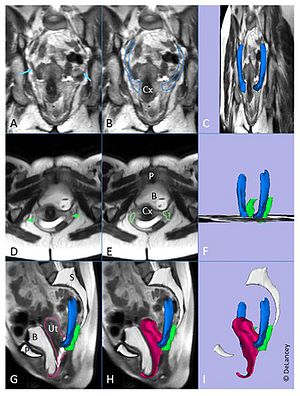

- 4.39 Using Stress MRI to Analyze the 3D Changes in Apical Ligament Geometry from Rest to Maximal Valsalva: A Pilot Study

- 6.10 Posterior Vaginal Prolapse Shape and Position Changes at Maximal Valsalva Seen in 3D MRI-based Models

- 6.17 Levator Ani Subtended Volume: A Novel Parameter to Evaluate Levator Ani Muscle Laxity in Pelvic Organ Prolapse

- 7.24 Segmentations of MRI Images of the Female Pelvic Floor: A Study of Inter- and Intra-reader Reliability